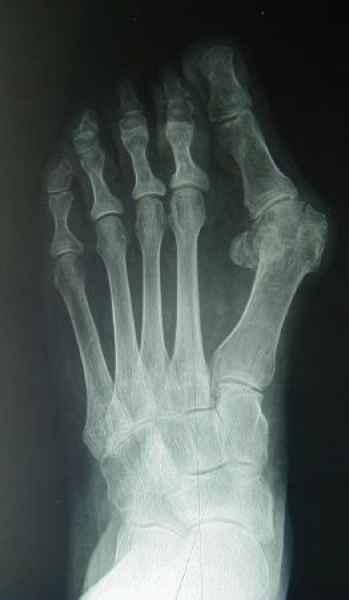

La marcha no solo es característica de la especie humana sino también de cada persona, y más aún varía según el estado de ánimo del momento. Una patología en los pies, se traduce en el rostro, en el ánimo, en el psiquismo. No sólo el dolor produce estos efectos, también un pie deformado o poco estético. En nuestra sociedad, la estética constituye un valor muy apreciado y estas alteraciones causan vergüenza fundamentalmente en las mujeres, que esconden en la playa sus pies en la arena y no pueden usar calzados elegantes.

Tanto la estructura del pie como su funcionalismo que es la marcha, pueden ser asiento y manifestación respectivamente de alteraciones locales ó sistémicas, por lo que su cuidadoso examen resulta de extrema utilidad diagnóstica.